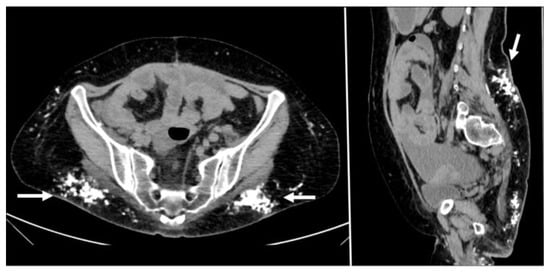

Figure 2. CT appearance of necrotizing fasciitis in a 58-year-old woman with a recent left lower limb open wound who arrived at the ER in septic shock. Arterial phase axial CT scan reveals the presence of free air in the fascial planes of the left lateral and posterior abdominal wall, with fascial thickening and lack of muscular enhancement, as compared to its counterpart (arrows). These elements are suggestive of necrotizing fasciitis. The patient was promptly referred to surgery, but she died on the operatory table.

On CT, the most suggestive findings of NF are the thickening of the fascia and a large amount of subcutaneous gas, although the latter is not specific [10,11,12] (Figure 2).

Focal or diffuse non-enhancing areas [10,11] with extensive multi-compartmental involvement (meaning that at least three muscle compartments are involved in this change) are another typical finding.